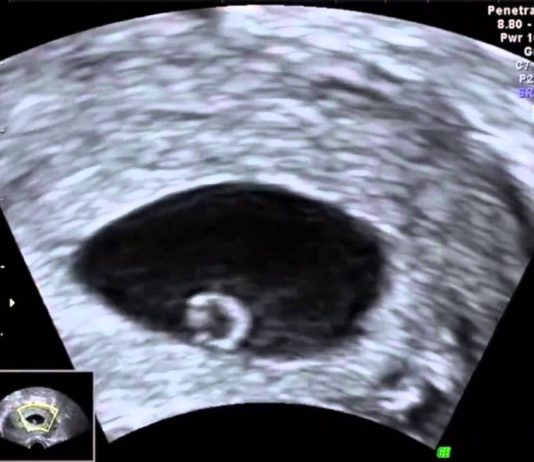

Gebeliğin/Hamileliğin 4. Haftası

Plesenta ve Embriyo Oluşuyor

Hamile olabileceğinizden şüphelenirken ve belki de doğum tarihi hesaplamaya çalışırken bebeğiniz evine yerleşti bile: İleride bebeğiniz olacak “blastosist” fallop tüplerden rahime...